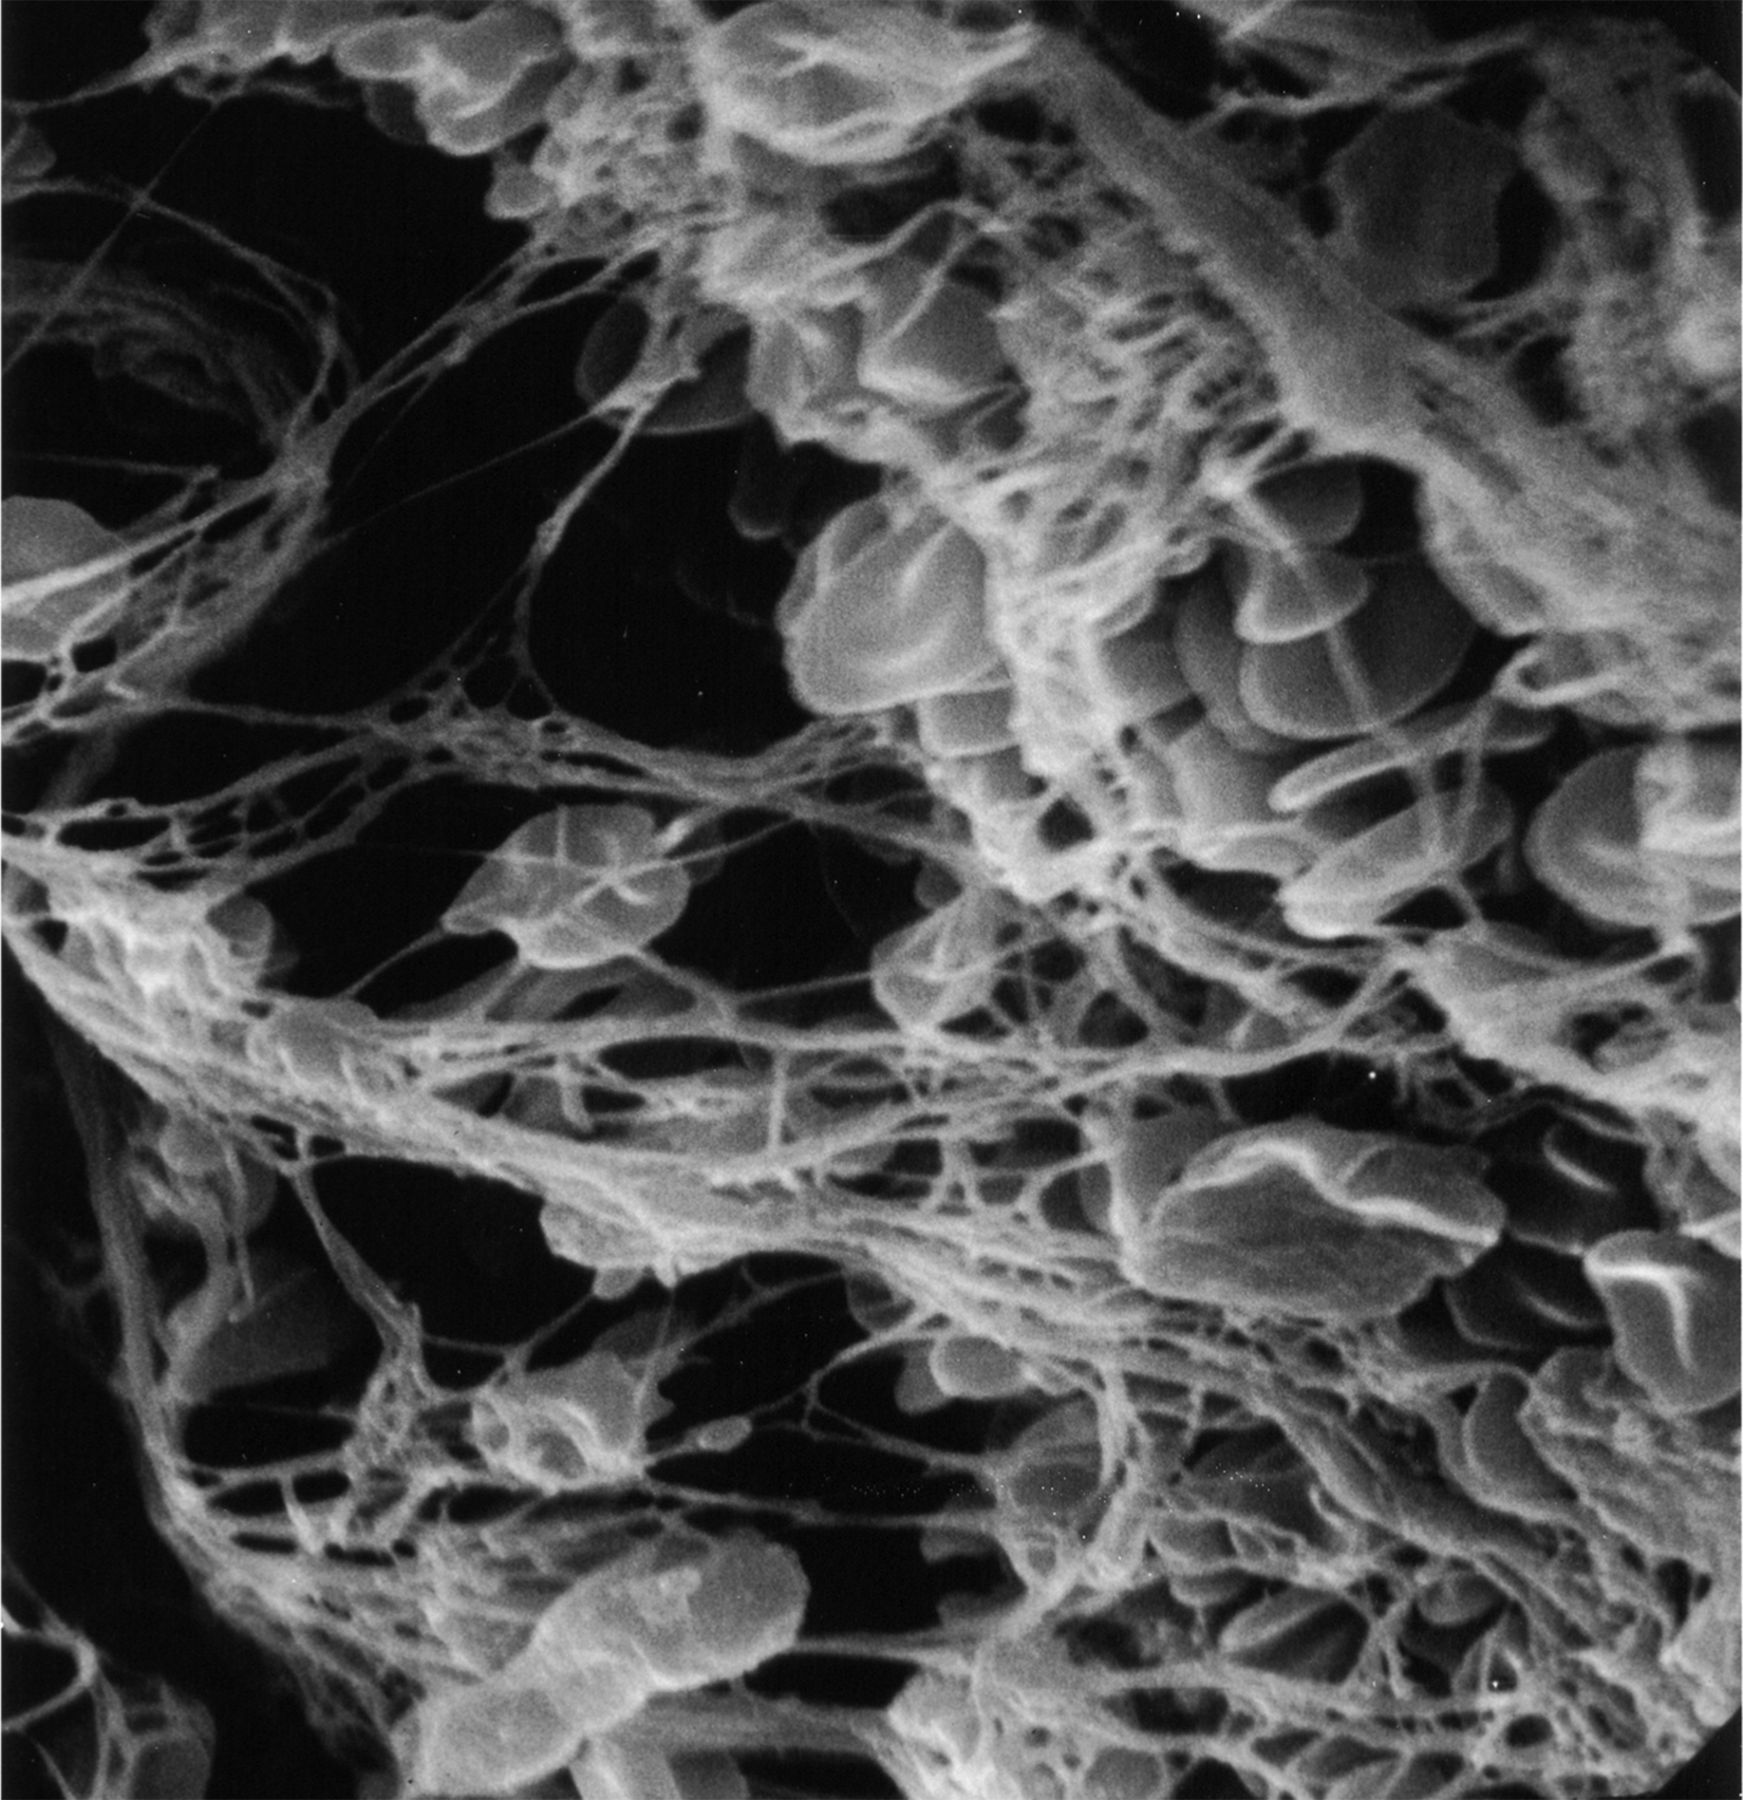

凝块被通过谢谢设备(n = 16), Accunet设备(n = 1),或直接与导游thrombo-aspiration导管阻塞网站(n = 1)。包括ICA(颈:n = 2;颅内:n = 7;两种:n = 1), MCA (n = 5)和基底动脉(n = 3)。宏观分析揭示了样本大小不同,形态和碎片。总值的光学显微镜标本显示特征暗示的一系列的流体动力学的力量可能是血栓。红色区域坐落在那里有可能低流或停滞或对血管壁的血栓,而白色区域有可能暴露在高剪切流(图1)。血栓性的组织元素,如纤维蛋白、血小板,红细胞,也不同在每个血栓和在各种血栓;因此,这些结果与早期的发现一致的组织学检查光学显微镜的凝块。12

这种血栓段特性相对光滑的表面形态。有强烈的白色和红色部分,表明暴露某些地区持续的高剪切流和其他地区停滞,分别。箭头表示位置的扫描电镜图片所示。

两个不同的结构模式与SEM可以认出:1)血栓展示先进成熟,所有的血栓性元素是如此密集集成单个实体没有清晰可辨的(图2),表明心脏稳定位置,持续暴露在剪切流;和2)血栓显示不同的纤维蛋白,红细胞被困,表明相对宽松的交联,一个活跃的地区特点的血栓仍在成熟的过程中,可能停滞的地区形成和再循环(图3)。这些模式被认为在不同比例在不同的患者。在某些情况下,可以联系具体的超微结构的研究结果推测病因的中风。值得注意的是这样一个广泛的血栓被恢复。